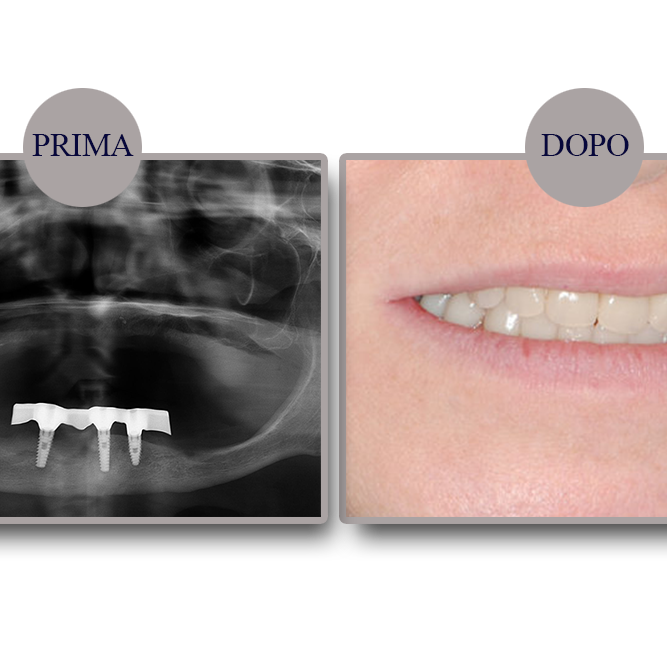

Ripristino dell’arcata superiore su overdenture su barra